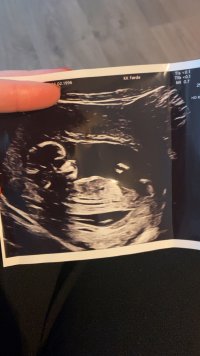

Ja du har et poeng, jeg var litt usikker på denne, men syntes blæra satt så lavt. Blir spennende å hørehvor mange uker og dager? umulig å si ut i fra 3D bildene, men synes jo at dette ser ut som klitoris og kjønnslepper.

Bildene ble tatt 13+0hvor mange uker og dager? umulig å si ut i fra 3D bildene, men synes jo at dette ser ut som klitoris og kjønnslepper.

Jeg vil endre svare mitt, at det er en jente, jeg tror det er den hula rett bak nuben som er blæra ikke den litt nedenfor som jeg først tenkte.Bildene ble tatt 13+0